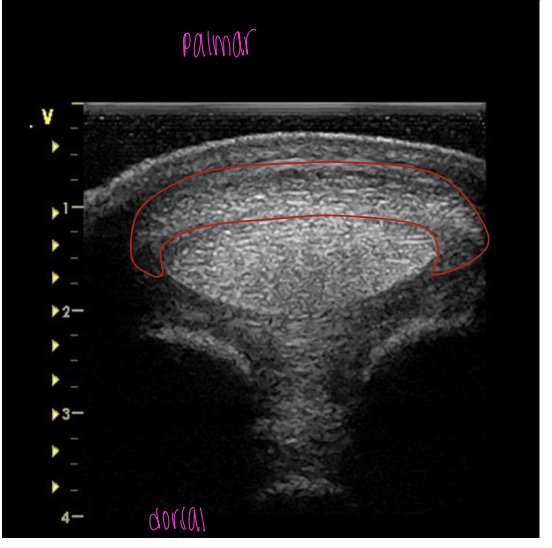

what is the red circling?

suspensory ligament at proximal MC 3

suspensory ligament at the mid MC 3

SDFT just below the carpal joint

SDFT at the mid MC 3

SDFT at the distal MC 3

SDFT at proximal fetlock joint